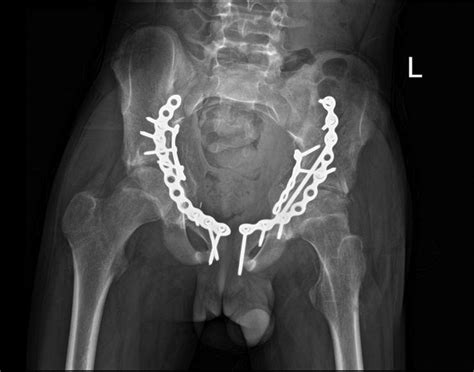

Bilateral Acetabular Fractures Induced By An Epileptic Seizure In A

Bilateral acetabular fractures induced by an epileptic seizure in a casereports.bmj.com

acetabular fixation pelvis bilateral fractures bmj casereports tab